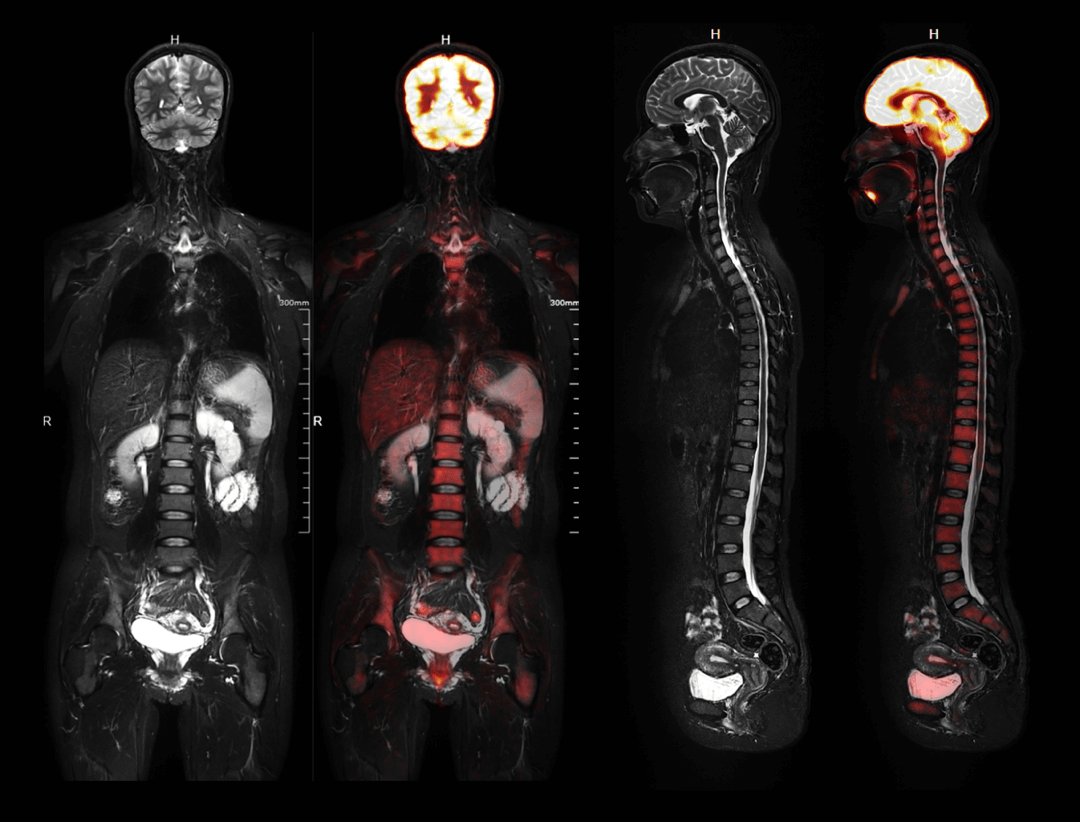

Whole-body Imaging with 4 bodies comparison

全身成像

• uPMR 790具有软组织分辨率好、多参数多序列成像、同时行功能性检查、无电离辐射等多项优势。同时,还可做到PET与MR信号同时采集,从而实现最佳的影像表现与功能信息显示,在全身疾病诊疗中的优势日益彰显。